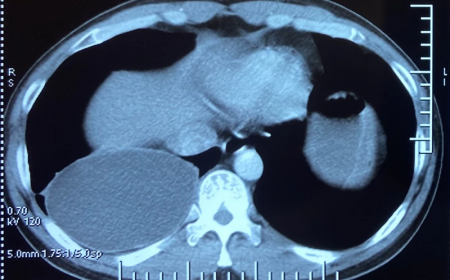

Trong số các bệnh ký sinh trùng nguy hiểm nhưng ít được chú ý tại Việt Nam, sán dây chó Echinococcus là một trong những mối đe dọa âm thầm mà chúng ta không nên...